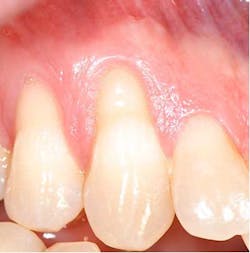

According to the proceedings from the 2014 American Academy of Periodontology Regeneration Workshop, root coverage may be attained through the application of a variety of surgical procedures. These outcomes are generally measured by reduced defect depth, gain in clinical attachment, and an increase in keratinized tissue. The associated systematic reviewprovides clear evidence that a subepithelial connective tissue graft (SCTG) procedure offers the best outcome for mean and complete root coverage, as well as an increase in keratinized tissue. (4,5) Strong evidence also supports biomaterials such as acelullar dermal matrix grafts (ADMG) or enamel matrix derivative (EMD) in conjunction with a coronally advanced flap (CAF) that can be used as an alternative to treat Miller Class I and II single-tooth gingival recession defects (figures 1 and 2). (6)Another suggestion from the proceedings was that using a split-thickness flap or tunnel technique can help to revascularize the graft by maintaining an excellent vascular supply to the flap.